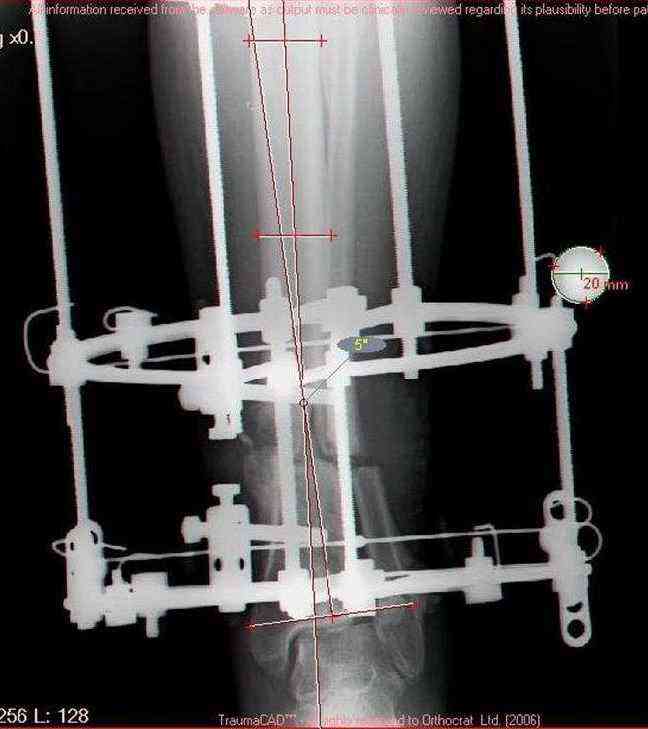

Sorry, I wiil tray now pictures of my case.